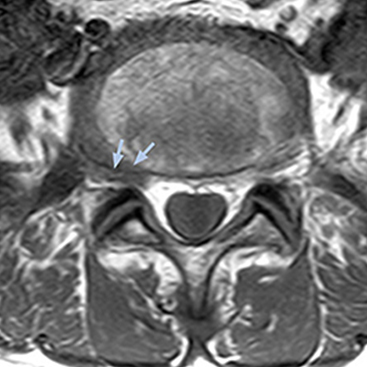

The key concept in MR neurography, Dr. Yabuki stresses, is the ability to directly visualize spinal nerves, versus inferring the presence of pathology indirectly. “Before NerveVIEW, we estimated compression of the nerve by looking for the presence or absence of fat signal on other MR images,” he says.

“For example, in sagittal images, when the presence of fat is observed in the intervertebral foramen, it suggests that there is a margin around the nerve. Similarly, the absence of fat indicates that the nerve is being compressed. So, we used to deduce nerve compression indirectly. With NerveVIEW, however, we can observe the condition of the nerves directly, regardless of the presence or absence of fat. We always prefer such direct observation of anatomy over having to make an inference about it.”